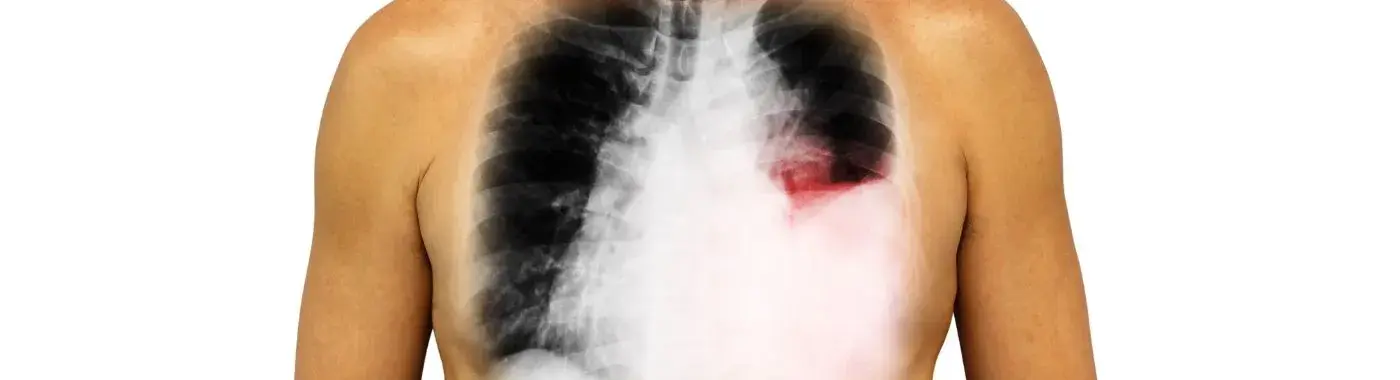

Pleural effusion is a medical condition characterized by the accumulation of excess fluid in the pleural space, the thin cavity between the layers of tissue that line the lungs and the chest wall. This condition can significantly impact respiratory function and overall health, making it essential to understand its causes, symptoms, diagnosis, and treatment options. Recognizing pleural effusion early can lead to better management and improved outcomes for affected individuals.

Pleural effusion is defined as the abnormal buildup of fluid in the pleural cavity. This space normally contains a small amount of lubricating fluid that allows the lungs to expand and contract smoothly during breathing. When excess fluid accumulates, it can compress the lungs, leading to difficulty breathing and other complications.

• Imaging Studies: Chest X-rays and ultrasound can help visualize the fluid. A CT scan may provide more detailed images.